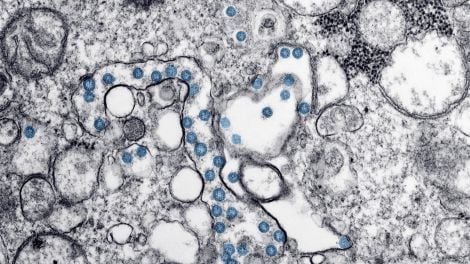

El documento, publicado en bioRxiv el 30 de abril, fue escrito por investigadores del Laboratorio Nacional de Los Alamos en Nuevo México. Durante dos meses, según el artículo, los autores han estado estudiando la evolución del SARS-CoV-2, el coronavirus detrás de covid-19. Para hacer esto, analizaron diferentes secuencias genéticas del virus tomadas de los pacientes a medida que la pandemia se ha movido por todo el mundo. Se han centrado principalmente en una parte clave del virus que le permite infectar células, conocida como la proteína espiga.